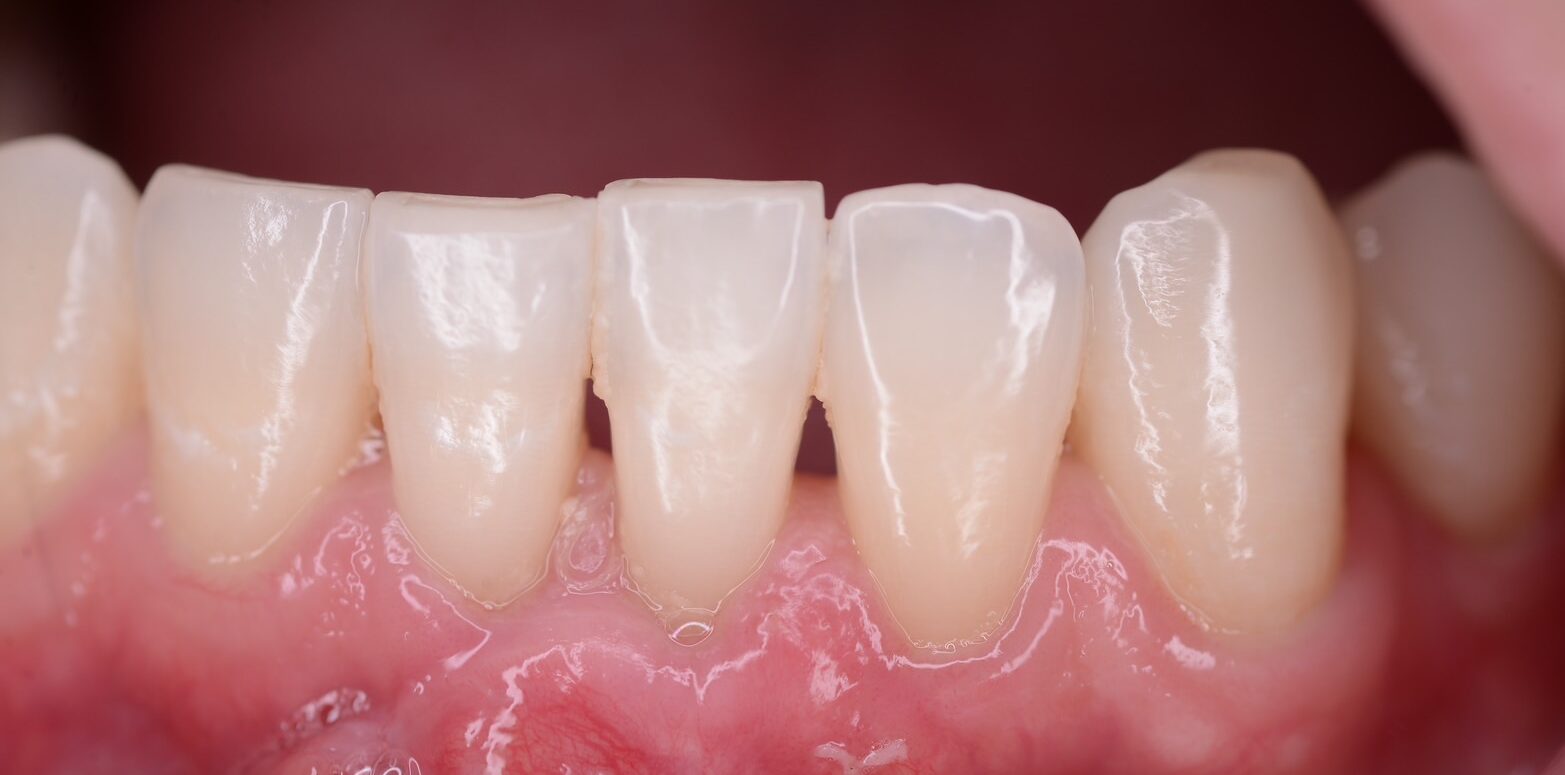

健康な歯肉状態

薄いピンク色の歯肉で、歯と歯の間に歯肉が適切に入り込んで弾力があります。歯肉が引き締まっており、ブラッシング時に出血することはありません。